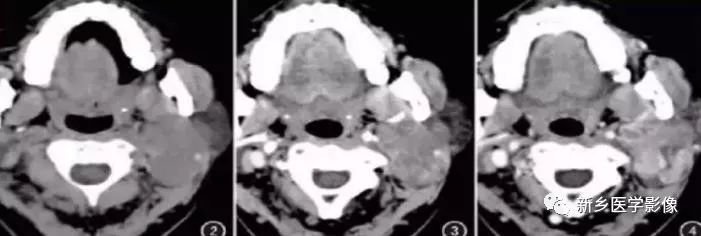

腮腺占位病变

1080x608 - 46KB - JPEG

腮腺良性肿瘤CT诊断与鉴别诊断~

1080x3113 - 589KB - JPEG